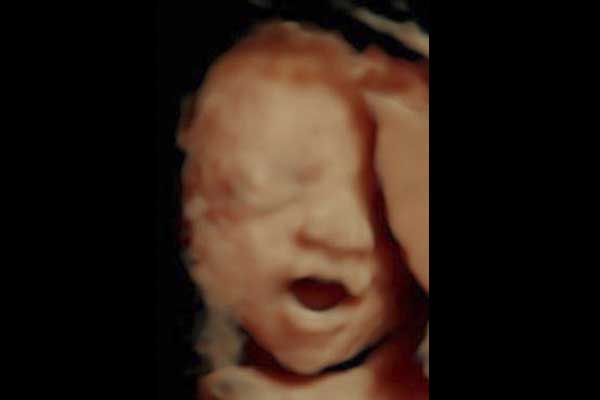

Ultrasonido en 3D

Reconstrucción digital de imágenes para formar una sola imagen en 3 dimensiones (3D), permitiendo así poder visualizar el rostro de su bebé.

La ecografía 3D es aquella que permite a usted ver la superficie corporal de su bebé, esto permite observar detalles como: labios, nariz, pómulos, frente, manos, entre otras.

Para lograr esto es necesario que se cumplan muchas condiciones como por ejemplo que el bebé no este mirando hacia atrás, que la placenta, el cordón o las extremidades no le tapen su rostro, así como que el líquido amniótico esté en cantidad suficiente.